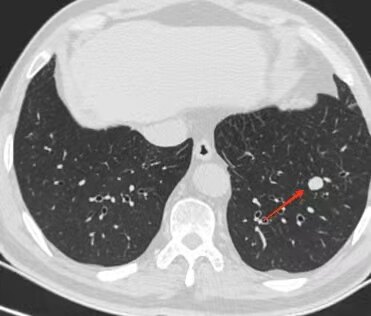

肺部囊腔类肺癌丨分型及其ct表现